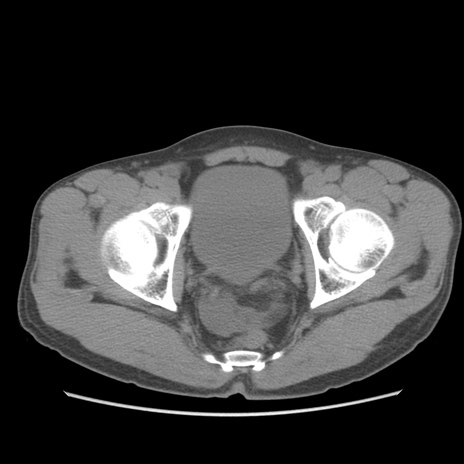

症例56 CT(横断像)

脂肪ウインドウ